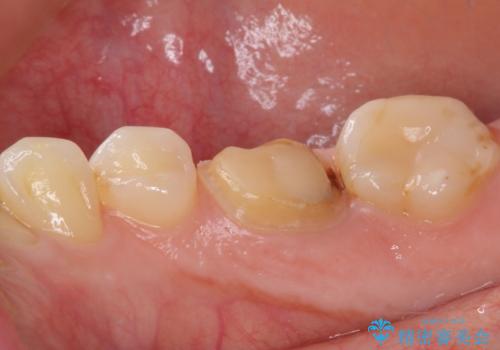

- 奥歯のクラウンが外れたままにしているとのことで来院された患者様です。

奥歯に特に症状はなかったのですが、排膿路が歯肉に認められたため、根管治療を行った上でオールセラミッククラウンにて補綴治療を行うこととしました。